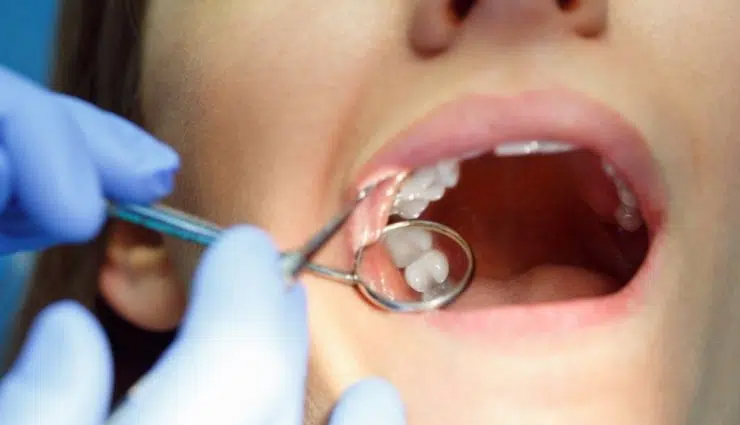

What happens during the removal procedure?

The wisdom tooth removal procedure can be performed under local anaesthesia, sedation, or general anaesthesia. The choice of anaesthesia will depend on the complexity of the procedure and your personal preferences.

Your oral surgeon will make an incision in the gum tissue to access the tooth and may need to remove some bone to access the tooth root. The tooth may be divided into sections for easier removal, and any remaining debris will be cleaned out. The gum will then be stitched up, and you'll be given aftercare instructions.